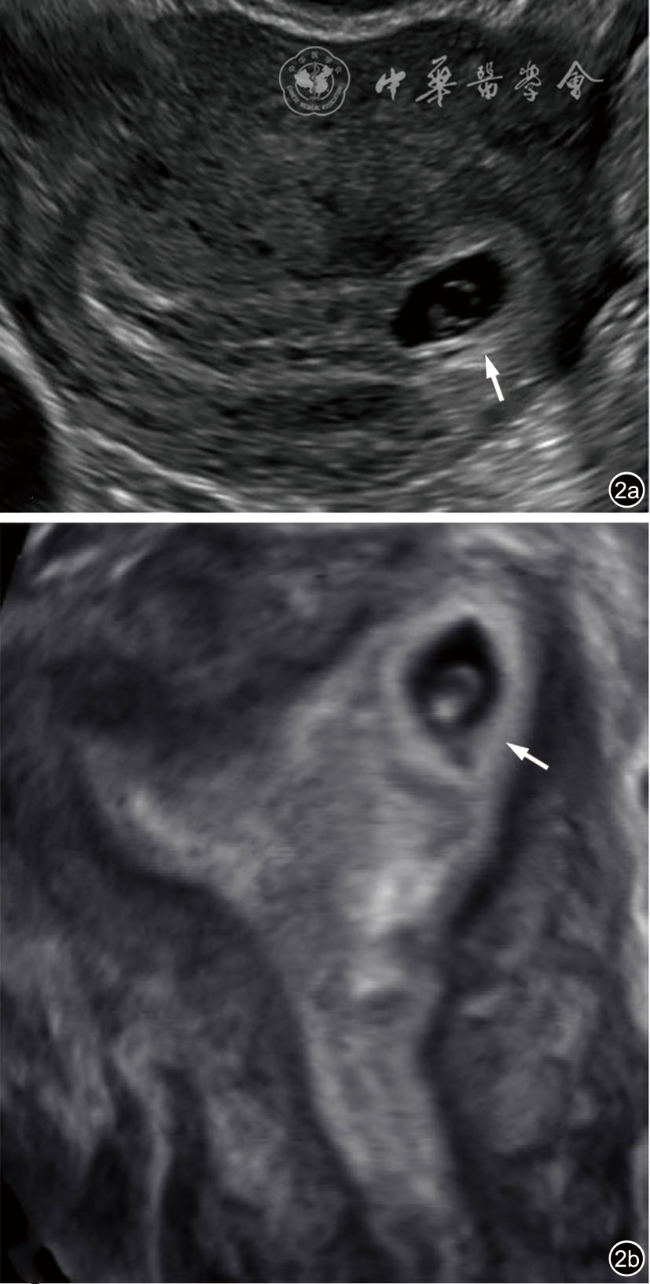

2.宫内妊娠的偏心着床(图2):指受精卵偏心着床于结构正常的子宫。正常妊娠的着床部位常靠近子宫中线,也偶可偏向左右侧,即偏心着床;此时,超声报告应提示为“宫内妊娠”或描述为“妊娠囊偏心着床但完全被子宫内膜包绕”,结论为“宫内妊娠”。该专家共识明确提出了应避免继续使用既往常用的‘宫角妊娠’‘宫角部妊娠’术语表述。

图2 宫内妊娠的偏心着床超声图像,妊娠囊位于偏心位置,但完全被子宫内膜包绕。图a为36岁孕妇(孕5周4天)经阴道超声横切面灰阶超声图,显示一偏离中线靠近左侧的妊娠囊(箭头所示)内含卵黄囊及胚胎。妊娠囊完全被子宫内膜包绕,可直接报告为“宫内妊娠”;也可补充描述为“妊娠囊偏心着床但完全被子宫内膜包绕”,但超声仍提示为“宫内妊娠”,以免与输卵管间质部异位妊娠混淆,避免使用‘宫角妊娠’或‘宫角部妊娠’等术语。图b为三维超声冠状面重建图,有助于确认妊娠囊位于子宫内膜内(图2译自参考文献[1])

考虑该专家共识对既往这一易混淆的临床问题提出明确的重新定义,是因为既往很长一段时间使用的‘宫角妊娠’,实际包含了“宫内妊娠的偏心着床”及“输卵管间质部异位妊娠”两种情况,短期超声随访或三维冠状面重建对两者的鉴别诊断较有帮助。